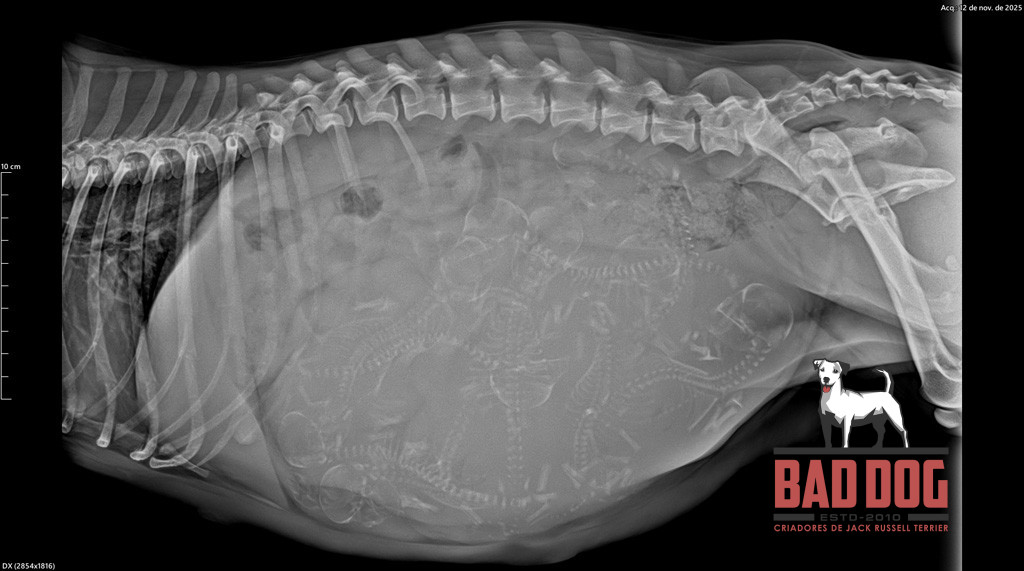

Ninhada PHI 2

Eco Oliva PHI2_oliva-rx2

3 of 36